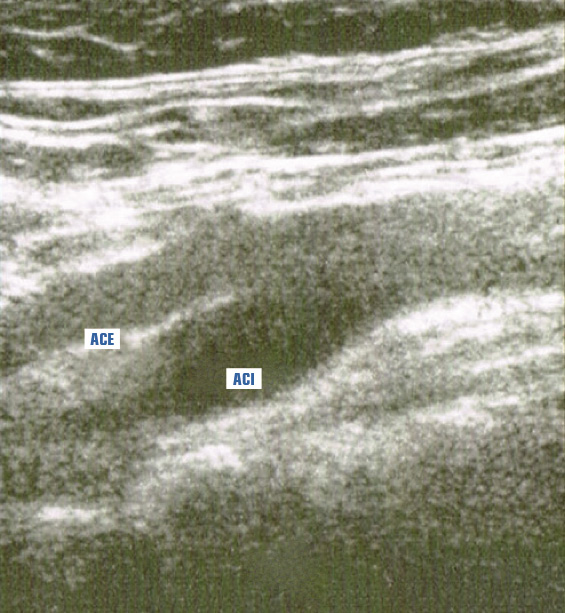

Il Doppler carotideo risulta normale, in particolare IMT (Intima-Media Thickness) < 0,9 mm (Figura 5).

Figura 5. EcoDoppler carotideo: IMT < 0,9 mm.

ACE = arteria carotide esterna; ACI = arteria carotide interna;